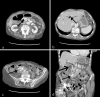

Gastric outlet obstruction secondary to biliary calculi: 2 cases of Bouveret syndrome